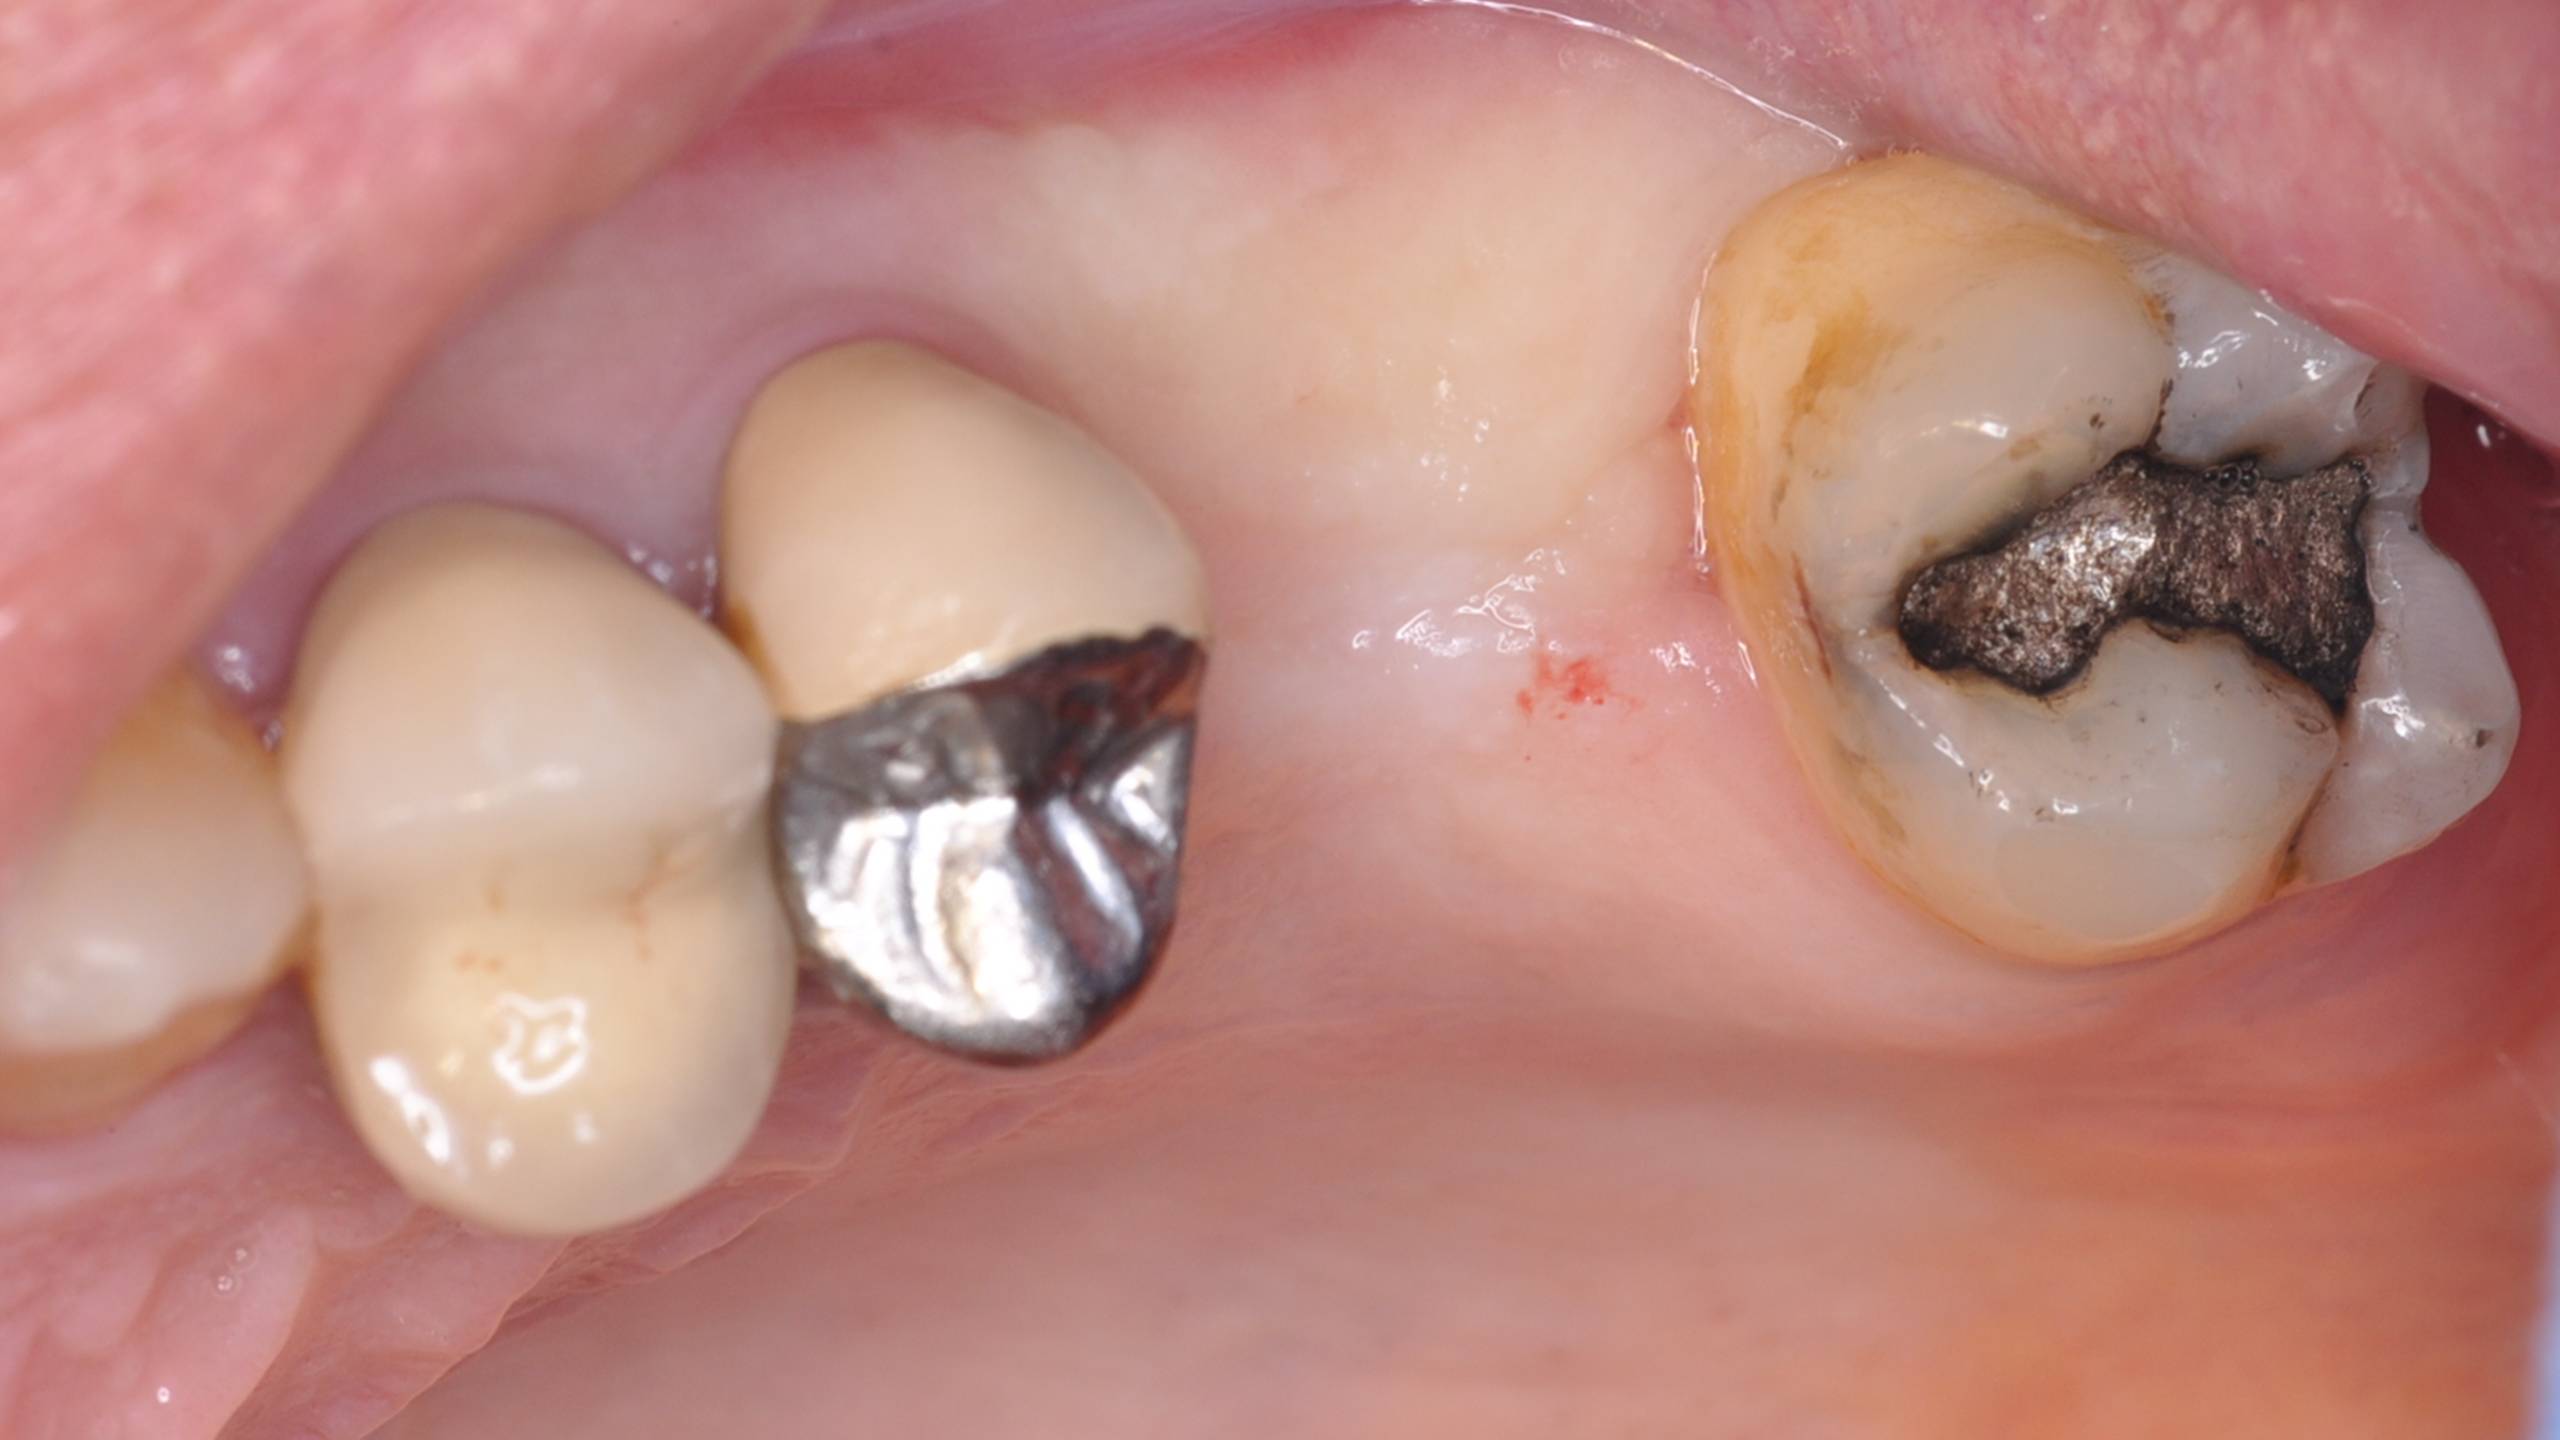

Patiente se présentant avec une récidive de carie sous une couronne.

Patient se présentant pour le remplacement de la 26 et 27.